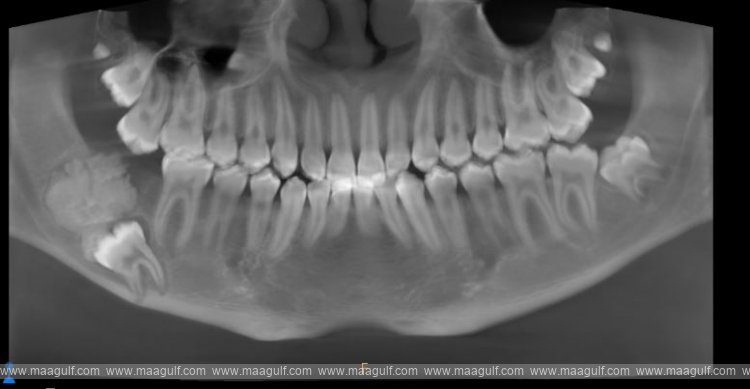

The family sought advice from several healthcare professionals who identified the rare nature of the swelling in the mouth. Since this required special treatment, Salem was eventually referred to Dr. Farzin Sarkarat, a specialist oral and maxillofacial surgeon at Medcare Dentofaces in Dubai. Concerned by the severity of the swelling in the boy's jaw and the displacement of Salem's right third molar tooth, Dr. Farzin conducted a thorough analysis.

“The position of the swelling was dangerously close to the inferior alveolar nerve, a critical nerve responsible for sensations in the lower teeth, chin, and lower lip. The tumor's proximity to the nerve made the situation extremely delicate, since any oversight could result in permanent nerve damage. This made the case highly complex. From the initial evaluation, it was clear that Salem’s condition was more than a simple swelling,” explained Dr. Farzin.

“Detailed imaging and diagnostic tests revealed that Salem suffered from Ameloblastic Fibroma, a rare benign tumour originating from dental tissue that typically affects younger individuals. While non-cancerous, the tumour caused significant swelling, pain, and displacement of Salem’s teeth,” he added.

“If left untreated, the tumour could have grown larger, damaging the surrounding bones and nerves, leading to facial deformities or even loss of sensation in the jaw,” said Dr. Farzin. “We decided to perform a surgical procedure to remove the tumor, preserve the nerve, and restore Salem's jaw.”

Dr. Farzin’s team designed a meticulous treatment plan that involved removing the tumor and impacted wisdom tooth, repositioning the nerve, and using a bone plate to reconstruct the jaw. Every step required extreme precision to avoid nerve damage and ensure Salem could regain full jaw functionality.